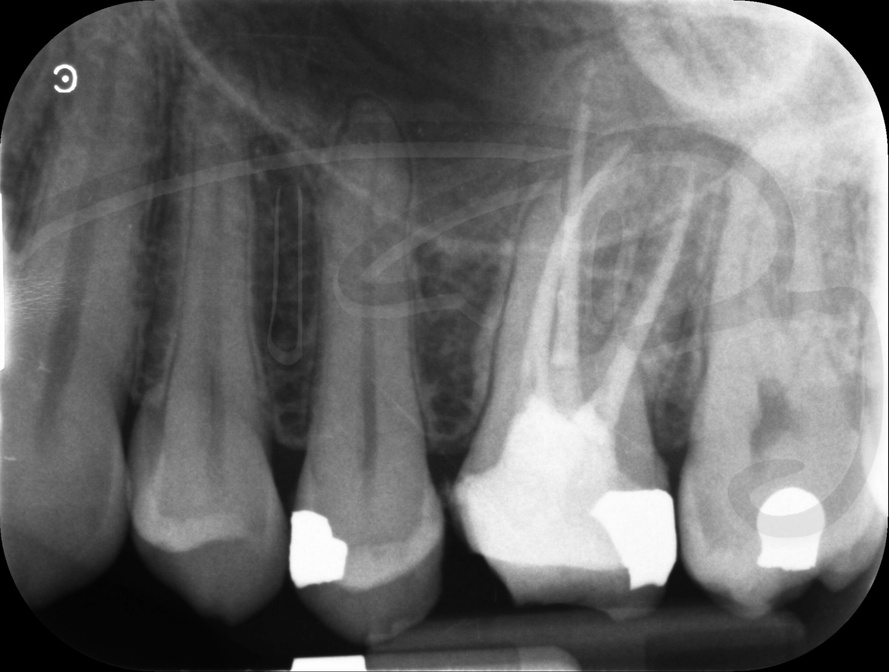

Endodontic Referrals

I am pleased to take endodontic referrals. Curved canals >30 degrees and potentially greater than 50 degrees can be negotiated. Sclerosed canals accessed. Post spaces prepared and the patient returned to you ready to restore.In most cases existing crowns, bridges and veneers can be retained with the endodontic access aesthetically restored after the full canal network has been treated.In the first instance I would prefer a radiograph and a brief list of patient expectations and a tooth history.

There are a number of ways to decide whether you need root canal treatment and the specific x-rays, scans and tests help diagnose your problem.An important sign is the type of pain you have been having with a tooth. It helps me decide if a tooth is in need of treatment and even if it saveable.

I really enjoy undertaking root canal treatments - rising to the challenge and helping people out of dental pain for the long term.I was privileged to be asked to speak at the 2016 BDA Conference, where I have a lecture about providing quality endodontic outcomes to patients, working as a generalist. Avoiding problems and pitfalls and maximising efficiency. One of the main matters that he covered was understanding that what is seen on plane radiography is utterly misleading and should not be the criteria by which a generalist continues treatment once it has been started.

At the 2016 BDA Conference, Thomas spoke about providing quality endodontic outcomes to patients, working as a generalist. Avoiding problems and pitfalls and maximising efficiency. One of the main matters that he covered was understanding that what is seen on plane radiography is utterly misleading and should not be the criteria by which a generalist continues treatment once it has been

started.